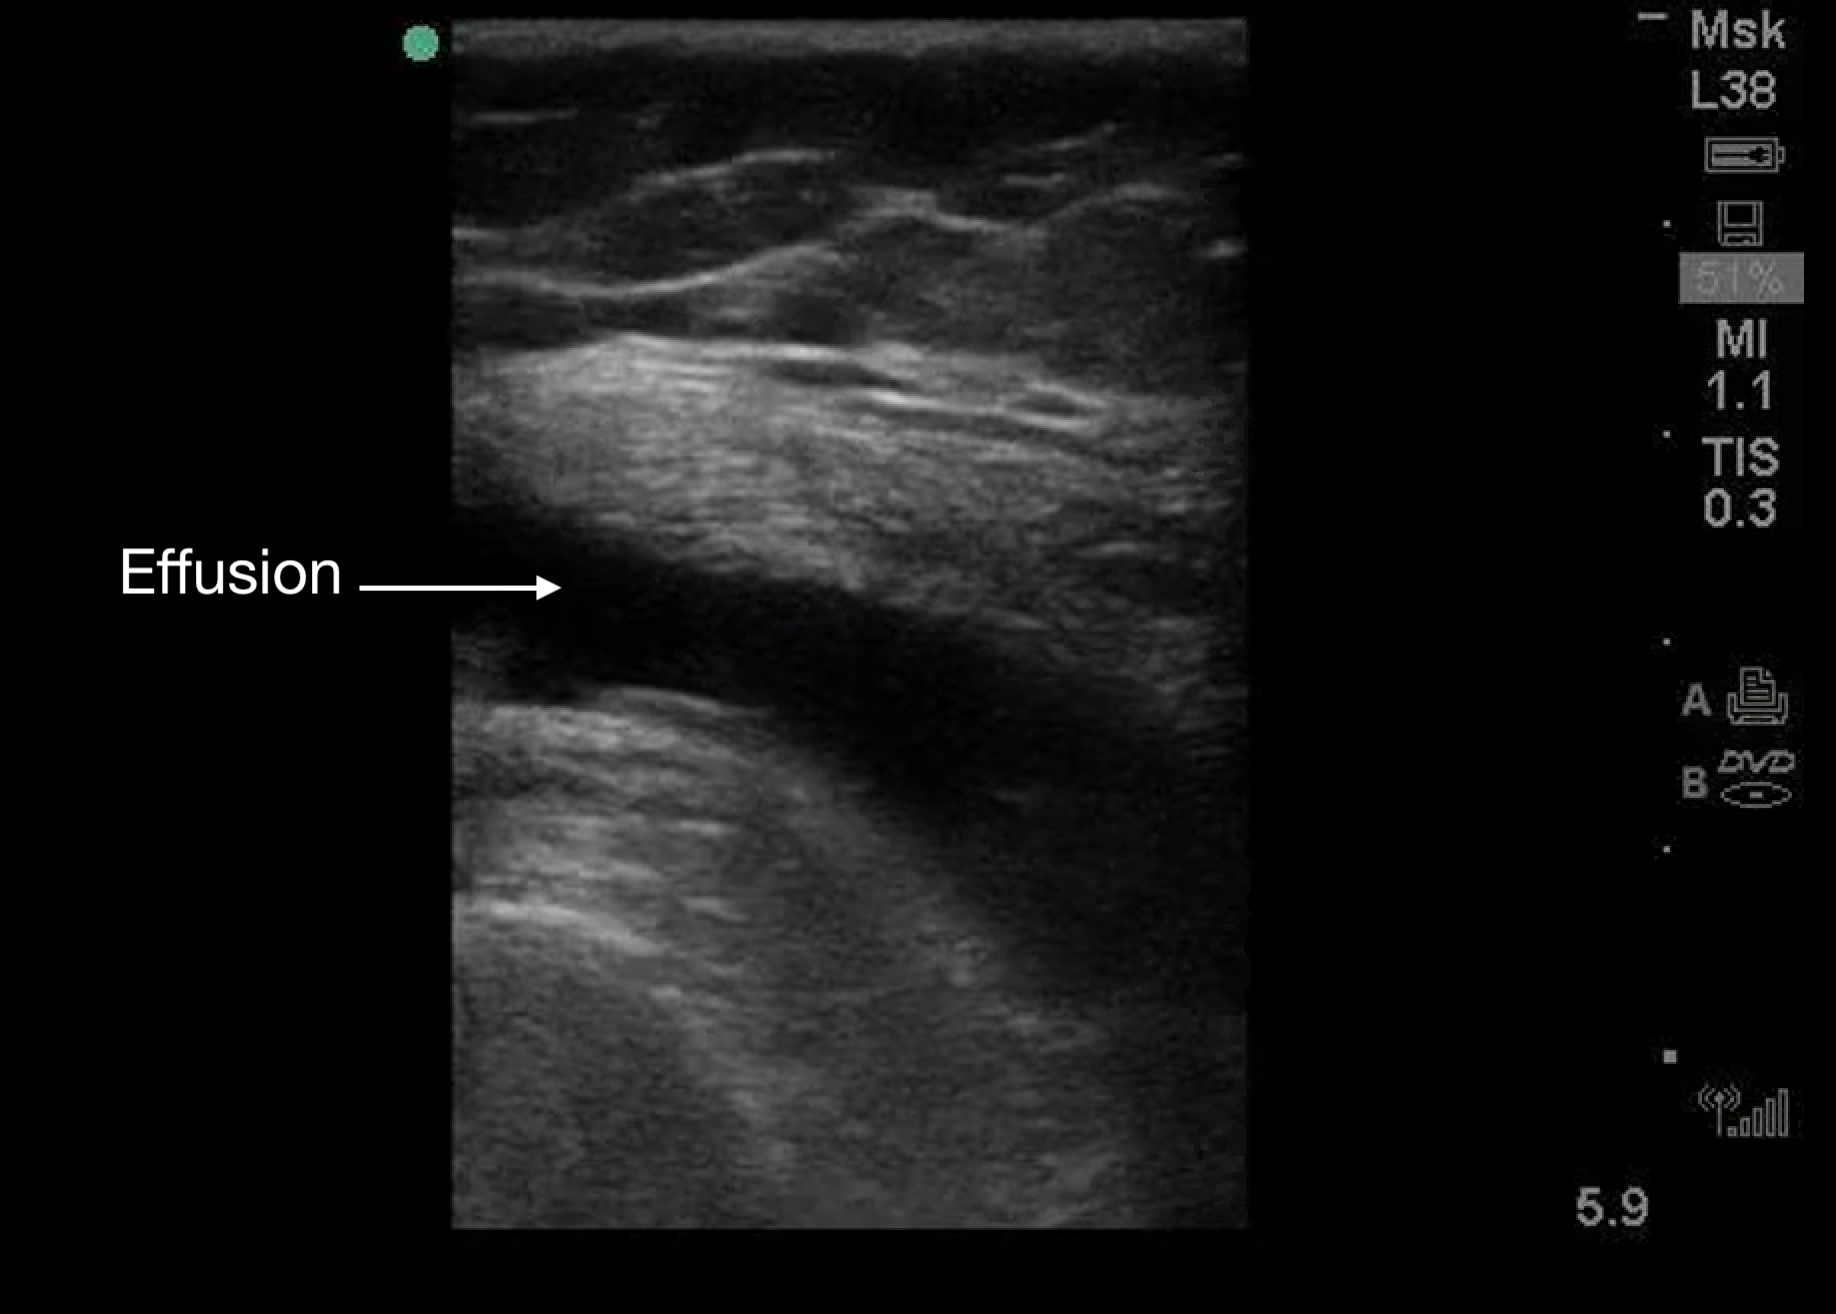

Appear as black (anechoic) areas within the joint space on ultrasound.

Figure 8.

A knee effusion seen with a linear transducer. Transducer positioning is the same as Figure 2C.

Presence of irregular internal echoes may indicate complex effusions due to:

- Hematoma.

- Pus.

- Fibrinous material.1

o POCUS is useful for guiding arthrocentesis, allowing precise aspiration of fluid from the joint space.3,5,9